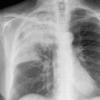

Case 1 Round pneumonia

Date: 04/16/2005

Views: 8483